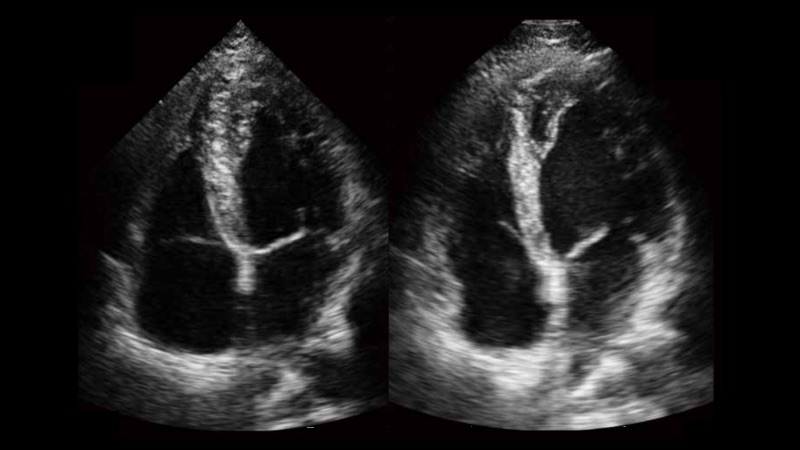

新一代微米成像技術(shù)大大提高了器官和病變的可見(jiàn)性。高清對(duì)比度分辨率將抑制斑點(diǎn)噪聲,同時(shí)保持真實(shí)的組織結(jié)構(gòu)。

自動(dòng)識(shí)別收縮和舒張末期心肌內(nèi)膜,自動(dòng)計(jì)算射血分?jǐn)?shù)EF值。